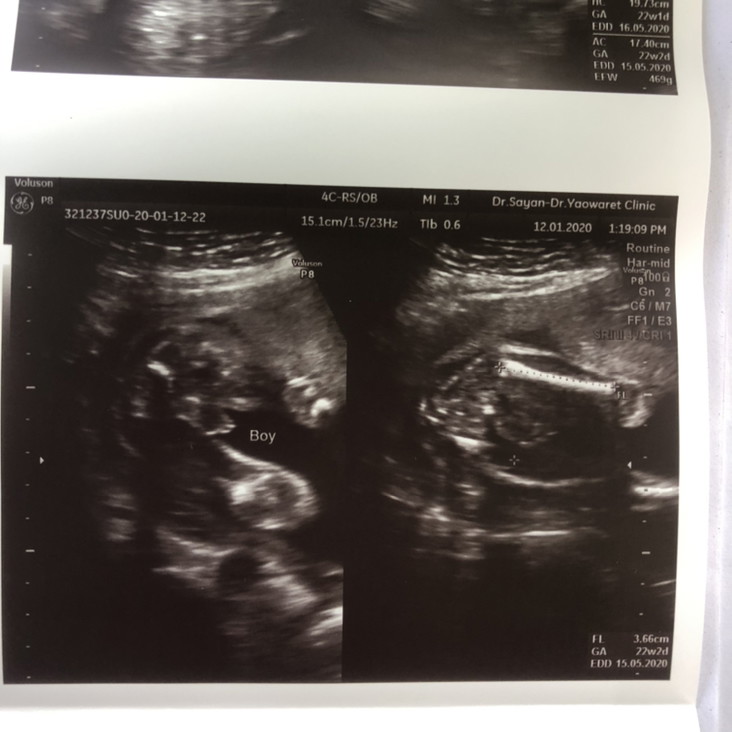

หมอเฟริมว่า เป็นเพศชาย แบบนี้มีอะไรผิดพลาดได้ไหมคะ

ชัดเจน ไม่น่าพลาดค่ะ

โอกาสพลาดน้อยมากค่า